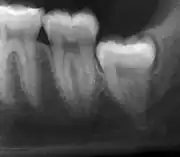

Asymptomatic disease-free impacted wisdom teeth in 21-year-old

The Cochrane review of surgical removal versus retention of asymptomatic disease-free impacted wisdom teeth suggests that the presence of asymptomatic impacted wisdom teeth may be associated with increased risk of periodontal disease affecting adjacent 2nd molar (measured by distal probing depth > 4 mm on that tooth) in the long term. Few studies, however, met the criteria to be included in the Cochrane review and those that were included provided very low quality evidence and had a high risk of bias. Another study which was at high risk of bias, found no evidence to suggest that removal of asymptomatic disease-free impacted wisdom teeth has an effect on crowding in the dental arch. There is also insufficient evidence to highlight a difference in risk of decay with or without impacted wisdom teeth.[17]

Due to the lack of sufficient evidence to determine whether such teeth should be removed or not, the patient's preference and values should be taken into account with clinical expertise exercised and careful consideration of risks and benefits to determine treatment.[28] If it is decided to retain asymptomatic disease-free impacted wisdom teeth, clinical assessment at regular intervals is advisable to prevent undesirable outcomes (pericoronitis, root resorption, cyst formation, tumour formation, inflammation/infection).[17]